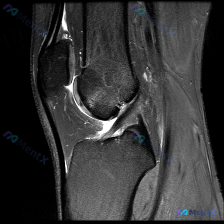

看到这张膝关节MRI矢状位T2序列的影像,整理一下分析思路,和大家一起讨论。

这是单张膝关节MRI矢状位T2序列影像,核心异常如下:

- 骨骼结构:股骨远端、胫骨近端、髌骨轮廓完整,无明显骨皮质断裂

- 韧带:前交叉韧带(ACL)走行可见,但近股骨附着点和中段低信号连续性不佳,周围有高信号影包绕;后交叉韧带走行和形态基本正常

- 髌下区域:Hoffa脂肪垫是最显著的异常区域——正常应该是均匀脂肪高信号,这里出现了明显的弥漫性信号增高、结构紊乱,提示水肿或炎症;髌腱本身显示完整

- 关节腔:髌上囊和髌下关节腔可见中等量积液(T2高信号),提示存在滑膜反应